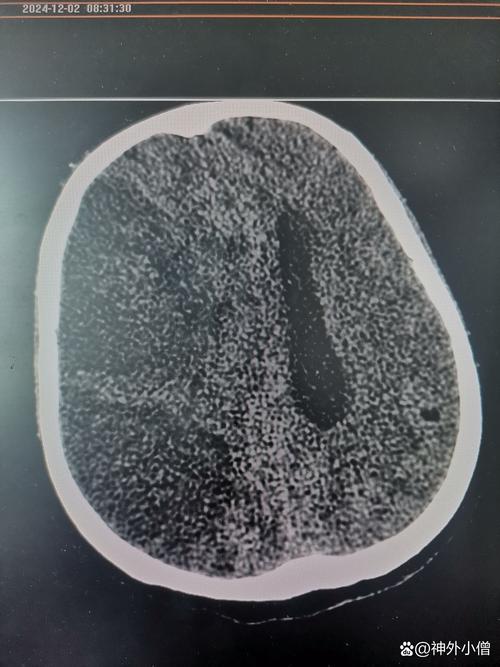

- 影像学检查(金标准):

- 头颅CT平扫: 可在早期排除脑出血,但发病6小时内可能看不到明显的梗死灶,仅见早期脑水肿的征象(脑沟变浅、脑室受压)。

- 控制颅内压: 使用甘露醇、高渗盐水等脱水药物,甚至去骨瓣减压手术(切除部分颅骨,让肿胀的脑组织有空间膨出),这是挽救生命的关键措施。